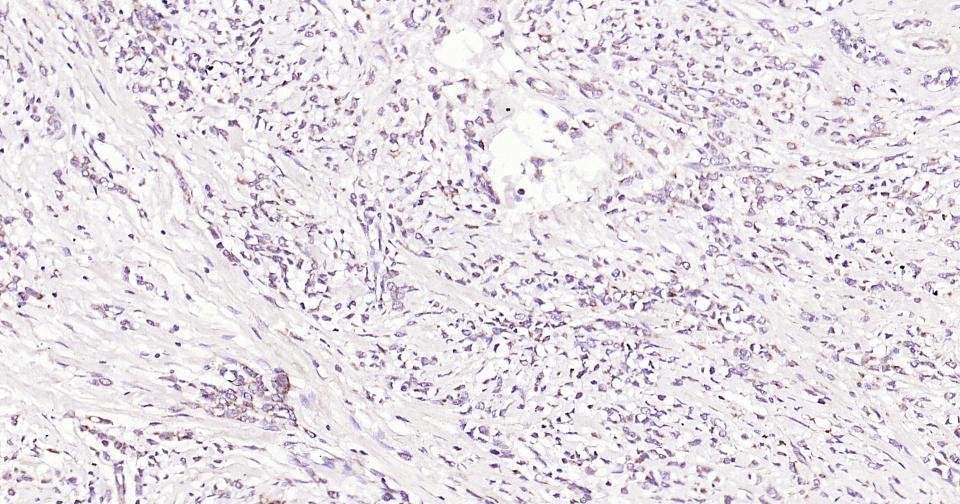

Paraformaldehyde-fixed, paraffin embedded Human Heart; Antigen retrieval by boiling in sodium citrate buffer (pH6.0) for 15 min; Antibody incubation with Bak Monoclonal Antibody, Unconjugated(bsm-61174R) at 1:200 overnight at 4°C, followed by conjugation to the SP Kit (Rabbit, SP-0023) and DAB (C-0010) staining.